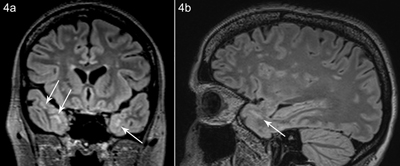

Figure 4

Patient B, coronal (a) and sagittal (b) FLAIR image shows white matter hyperintensity subcortical anteromedial in the temporal lobe.